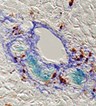

For chronic injury, the liver uses a back-up system that stimulates stem cells to proliferate and eventually differentiate into new liver cells. Greenbaum and colleagues found that these dual-potential stem cells can be identified and potentially isolated from other liver cells because they uniquely express the protein Foxl1. The team showed that in two mice models of liver injury, stem cells and their descendents were marked by the expression of FoxL1. The researchers propose to use this marker to isolate the Foxl1-bearing stem cells and transplant them back into damaged livers to restore function.